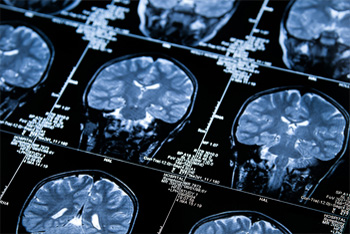

The PREVENT Dementia study aims to identify the earliest signs of dementia, which scientists believe may occur in the brain decades before symptoms appear.

MRI Scans